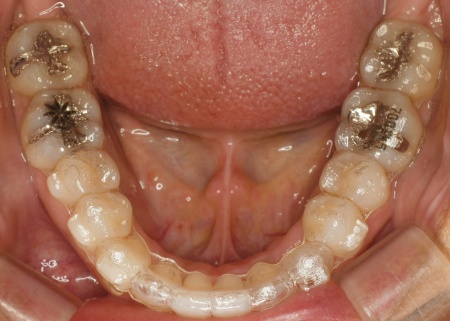

そのため、今回はマウスピース型矯正装置「インビザライン・コンプリヘンシブ」による矯正治療と、舌の癖を改善するトレーニング「MFT(口腔筋機能療法)」を併用することを提案し、同意いただきました。

インビザライン・コンプリヘンシブは、幅広い症例に対応可能で、マウスピースを段階的に交換しながら歯を少しずつ動かしていく方法です。

今回は、奥歯を少し押し込みながら前歯が噛み合うように治療を行う方針です。

患者様には、マウスピースの装着方法やお手入れの注意点、1日20時間以上装着すること、1〜2週間ごとに新しいマウスピースに交換することなどを丁寧にお伝えしました。

また、治療の際は上下の歯にかける「顎間ゴム」を併用しています。

これは上下の歯の位置関係を調整し、前歯の噛み合わせを整えるためのものです。